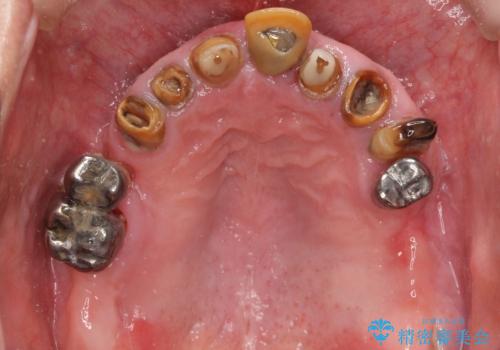

- 歯がぐらぐらで咬めないことを主訴に来院された患者様です。

他院では上顎骨が薄いためインプラントできないと言われたとのことでした。

精査したところ、歯周病に罹患した歯を長年放置したことから骨吸収が進行し、上顎骨の厚みはとても薄くなっていました。

全顎的な歯周病治療を行ったのち、上顎洞底挙上術(上顎骨に骨を増やす手術)を併用したインプラント埋入を行いました。